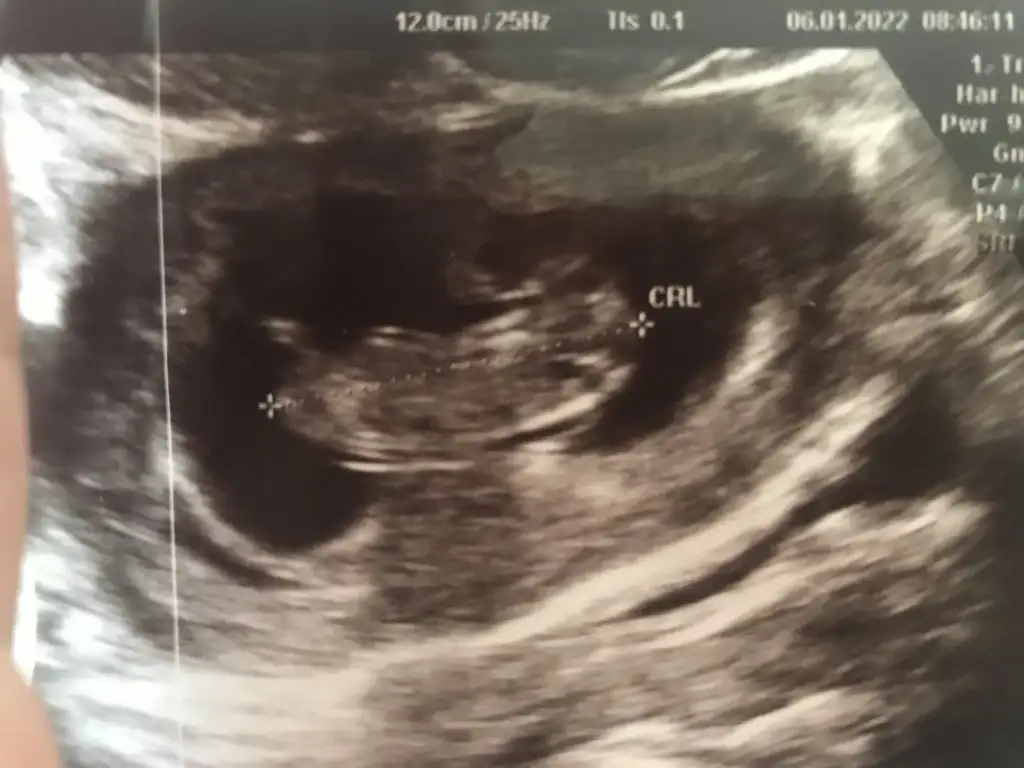

Merhaba Ikra meyra 10+4 CRL de 11+2 çıktı. Cinsiyet tahmininde bulunabilir misiniz?

Teşekkür ederim